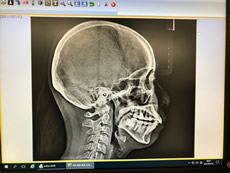

歯科用CT(3Dレントゲン)及びセファロ(矯正治療用レントゲン)

通常歯科用CT(3Dレントゲン)を導入する場合は主にインプラント治療のオペシュミレーション用が主な理由だと思われますが、当院は、基本的にインプラントは積極的におすすめしておりません。 この3Dレントゲンによって、出来る限り幹部を絞り込んで撮影し、「根尖病巣(こんせんびょうそう)」を見つけつためであり、また、実は根尖病巣は歯だけでなく、副鼻腔や顎の骨、手足にも症状が出ることがあるのです。

また、この歯科用CTはセファロ(矯正治療用レントゲン)としても機能し、今まで2Dで撮影し歯の並びをシュミレーションしていた次回から3Dで歯並びを把握し、また、「アデノイド(鼻と咽の間にあるリンパ組織)の大きさ」まで把握しながらの矯正治療が可能になります。